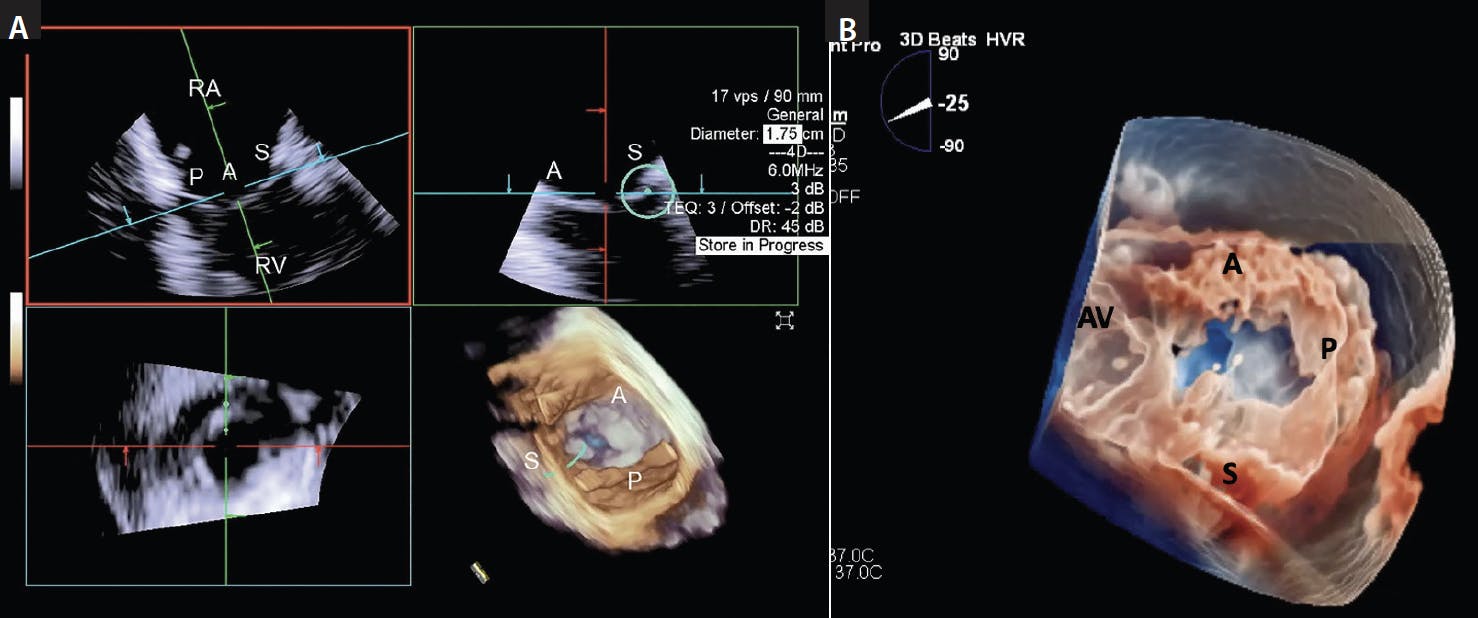

Figure 6. MPR view identifying the TV leaflets in 3D views. Once the RV inflow view (upper left panel) is acquired, multiplane feature simultaneously identifies the orthogonal view (upper right panel), with an en-face reconstructed 2D view (bottom left panel) and 3D en-face atrial view (bottom right panel) with the AcuNav catheter (A) and using the VeriSight Pro (B) in real time. The green circular cursor can be placed to identify the septal, anterior, and posterior leaflet on multiple views. AV, aortic valve.

Orthogonal views with biplane or real-time 3D MPR can be displayed simultaneously (Figure 7). The tricuspid clip is opened above the TV, aligned above the TV, and advanced into the RV just below the targeted leaflets with the orthogonal views as guidance. If the desired grasping area is located along the anteroseptal commissure, the grasping view will typically show the anterior and septal leaflets on top of the tricuspid clip arms (Figure 8). The absence of acoustic interference of the CDS at the level of the tricuspid leaflets is a distinct imaging advantage with 3D ICE. This facilitates proper leaflet grasping with no need for catheter manipulation, allowing the operator to maintain the delivery system in plane throughout grasping. Crosshair alignment of the image is used to properly orient the clip with TV leaflets, confirming of insertion of both anterior and septal leaflets. Doppler flow is used to determine residual regurgitation and need for additional clip placement.

When additional clips are necessary, TEE biplane imaging is used to align the TV leaflets, and there can be acoustic interference created by the first clip, as well as the clip delivery catheter. Three-dimensional ICE biplane imaging or MPR minimizes the chance of acoustic interference as the imaging catheter lies directly behind the CDS. Proper alignment of the subsequent clip is performed after the same procedural steps as the first clip. MPR is routinely used for the second clip, aligning the crosshairs to the second clip to optimize and confirm leaflet grasping.